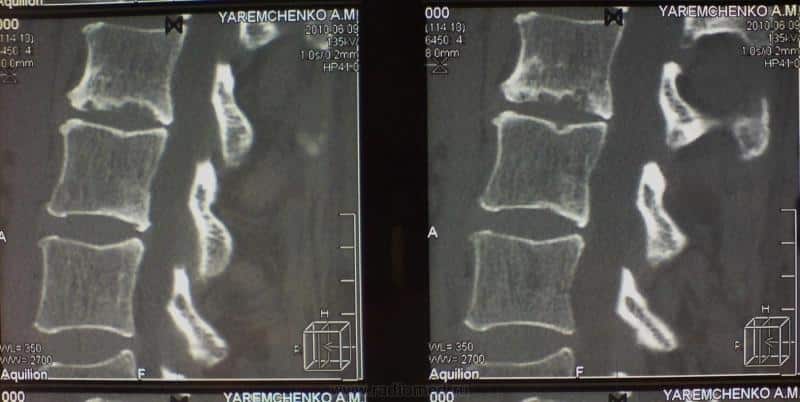

Диагностика заболевания основывается на анамнезе, собранном врачом, и конкретных жалобах пациента. Обычно методы рентгенографии и магнитно-резонансной томографии позволяют выявить патологии в межпозвоночных дисках. На снимках можно заметить неровные края, сужение дисков, их износ и другие изменения.